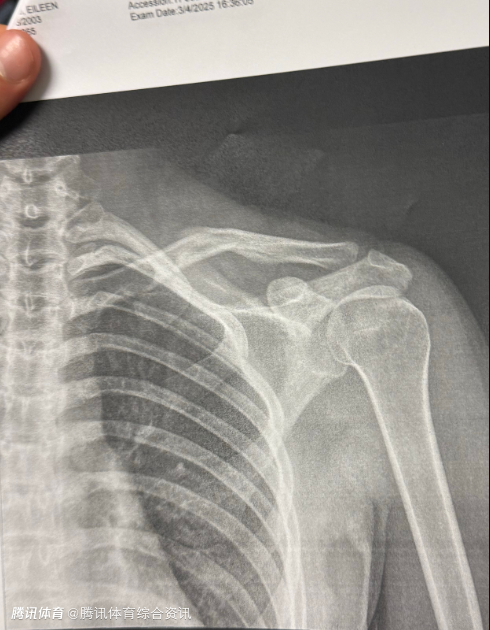

2025-03-09 10:20北京时间3月9日,奥运冠军谷爱凌更新社媒,晒出骨折X光照,并配上一个心碎的表情。

从图片上看,X光照的日期是3月4日,目前尚不清楚谷爱凌本次的伤病是新伤还是旧伤。

上个月谷爱凌在训练中不幸再次受伤,宣布不得不退出亚冬会。当时她发文表示:“我在Aspen Xgames比赛受伤后,为了能参加紧接其后的世界杯比赛,在训练中不幸再次受伤。今天我不得不怀着沉重的心情退出盼望已久的哈尔滨亚冬会。中国运动员们取得最好的成绩。我也会积极配合医生康复治疗,争取本赛季尽快回到赛场。”